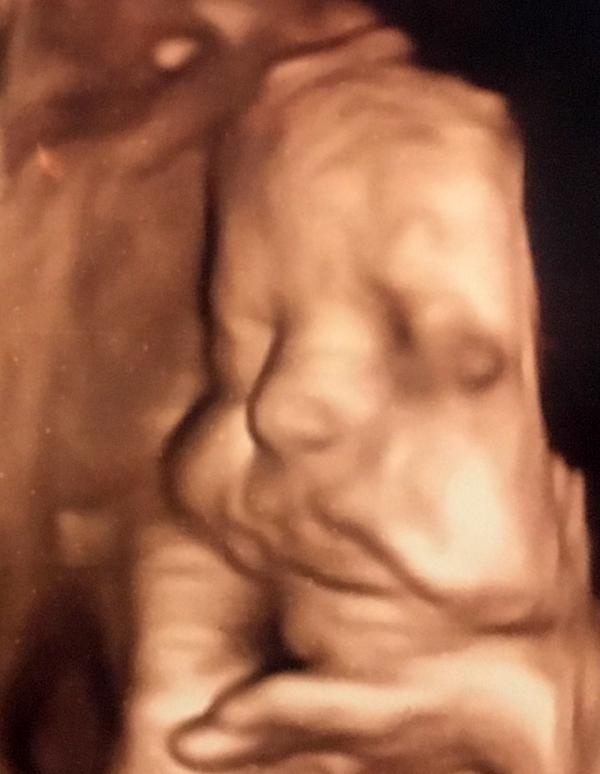

20 Weeks On Friday Find Out What We Re Having On Sat D Bebek Ultrason Bebek Gelisi Bebek

Anne Karnindaki Bebeklerin Gulumseten Pozlari Foto Galerisi